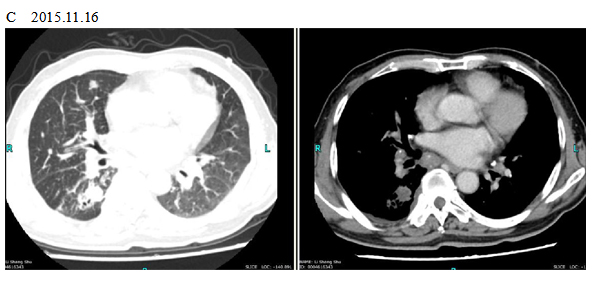

A 66-year old male patient with a smoking history was received by the Outpatient Department on September 14, 2015 due to “coughing for more than one month”. Main symptoms included a dry cough, a small amount of white phlegm, but freedom from fever, chest pains, bloody sputum, and any other discomfort. Stage IV-lung cancer is associated with anorexia and a loss of nearly 10 pounds. The patient had a poor constitution in the past, with a history of “acute hepatitis”, “type-2 diabetes” and “obsolete pulmonary tuberculosis”. The patient was accepted in the Department of Respiratory Medicine on September 15. The results of a lung CT scan indicated a “space occupied for posterior basal segment of right inferior lung and enlarged for mediastinal lymph nodes”. The patient was approved for a CT- guided transthoracic needle biopsy, immunohistochemistry, EGFR gene mutation detection, and systemic metastases assessment. He was diagnosed as “primary lung cancer, right lung adenocarcinoma, T4N3M1B (lung, pleura and brain), and stage-IV EGFR Exon 19 deletion mutation (Fig. 1A and Fig. 2A)”.

The patient checked for further treatment on November 23, 2015. A pre-chemotherapy assessment was made and the results showed multiple bone metastases and multiple enlarged lymph nodes in the left shoulder blade, the fourth lumbar, the right iliac bone and other locations. Performance status (PS) was only one point. Pemetrexed Disodium (500 mg/m2 d1) + Carboplatin (AUC 5 d1) + Bevacizumab (7.5 mg/Kg d1) was administered beginning November 26, 2015 for the chemotherapy treatment and supportive therapy was provided, such as, dehydration, reduction of intracranial pressure, promotion of bone repair, pain relief, and waist protection. After discharge, the coughing basically disappeared and the dizziness, backaches, and hemiparesthesia of the left side were significantly improved. Patient emotional state and sleep quality was significantly improved. It was basically normal after a routine blood examination. A second chemotherapy treatment was successfully completed on December 18 (the program is idem). The patient returned to the hospital on January 6, 2016 and was proposed for a third chemotherapy. The pre-chemotherapy assessment showed that the measurable, targeted right lung lesion had decreased (3.2 mm, with a rate of decrease 44.8 %) (Fig. 1D). Lymphangitis carcinomatosa was significantly decreased and right frontal nodulus lesions were reduced significantly (Fig. 2C). No new lesions were found. Efficacy was assessed as partial relief (PR). A third and fourth chemotherapies were completed on January 9 and January 30, 2016. Efficacy was re-assessed as PR (Fig. 1E) with lung CT review as an outpatient on February 11. Since then, the patient had been subjected to a combined administration program of pemetrexed disodium (500 mg/m2 d1) + bevacizumab (7.5 mg/Kg d1) for continued chemotherapy. A lung CT and a cranial MRI were peformed on April 16. The results showed that the control of lung lesions and intracranial lesions were basically the same as before (Fig.1F and Fig. 2D). The patient had no cough, backaches, or hemiparesthesia and the quality life significantly improved. PS was decreased to zero.